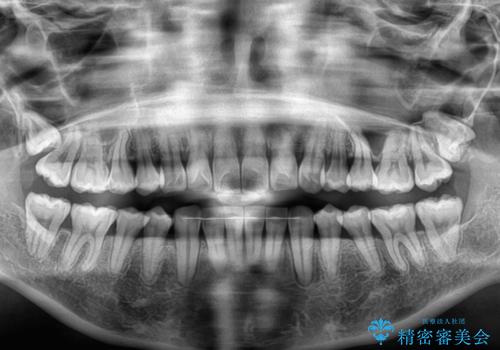

- 上下前歯の叢生を気にして来院された患者様です。

インビザラインでの治療を希望されていて、デコボコの程度が中等度であり、安価なパッケージにて対応可能と判断されたため、インビザライン・モデレートを用いて矯正治療を行うこととしました。

インビザライン・モデレートは、製作できるアライナーの枚数に制限があるため、移動可能な量に限りがあるものの、インビザライン・ライトよりも枚数が多いため、幅広い症例に対応可能です。